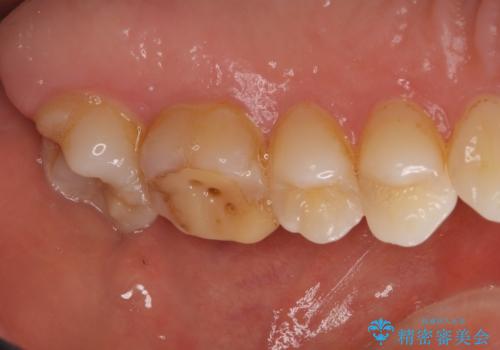

- 他院で自費根管治療、矯正治療、セラミック治療をする予定でしたが、根管治療終了後から忙しく通わなくなり放置していました。

海外転勤が決まったため、それまでに治療をしてほしいとご来院されました。(矯正治療はせずにセラミック治療のみ)

海外転勤が決まり、急いでセラミック治療をしてほしいとご来院された患者様です。

根管治療に症状がなく、上の歯に関しては土台もそのまま使用可能であったため、下の歯の土台、上下の歯のセラミック治療を行いました。

今回は幸い、症状がなく、根管治療の再治療が必要でないため、円滑に治療を進めることができました。